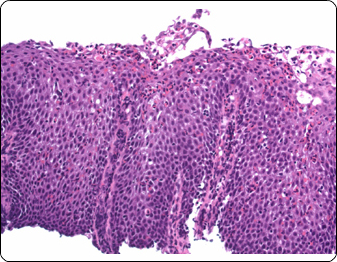

As a sub-specialty laboratory specialized in gastrointestinal and liver pathology, as well as women health, dermatology, head and neck and urology; Specialized Pathology Laboratories is your best choice for biopsy services. Our experienced team utilizes the latest technologies to provide physicians with the most accurate results. We deliver reports on time, reduce diagnostic inaccuracy and enable higher levels of medical treatments.